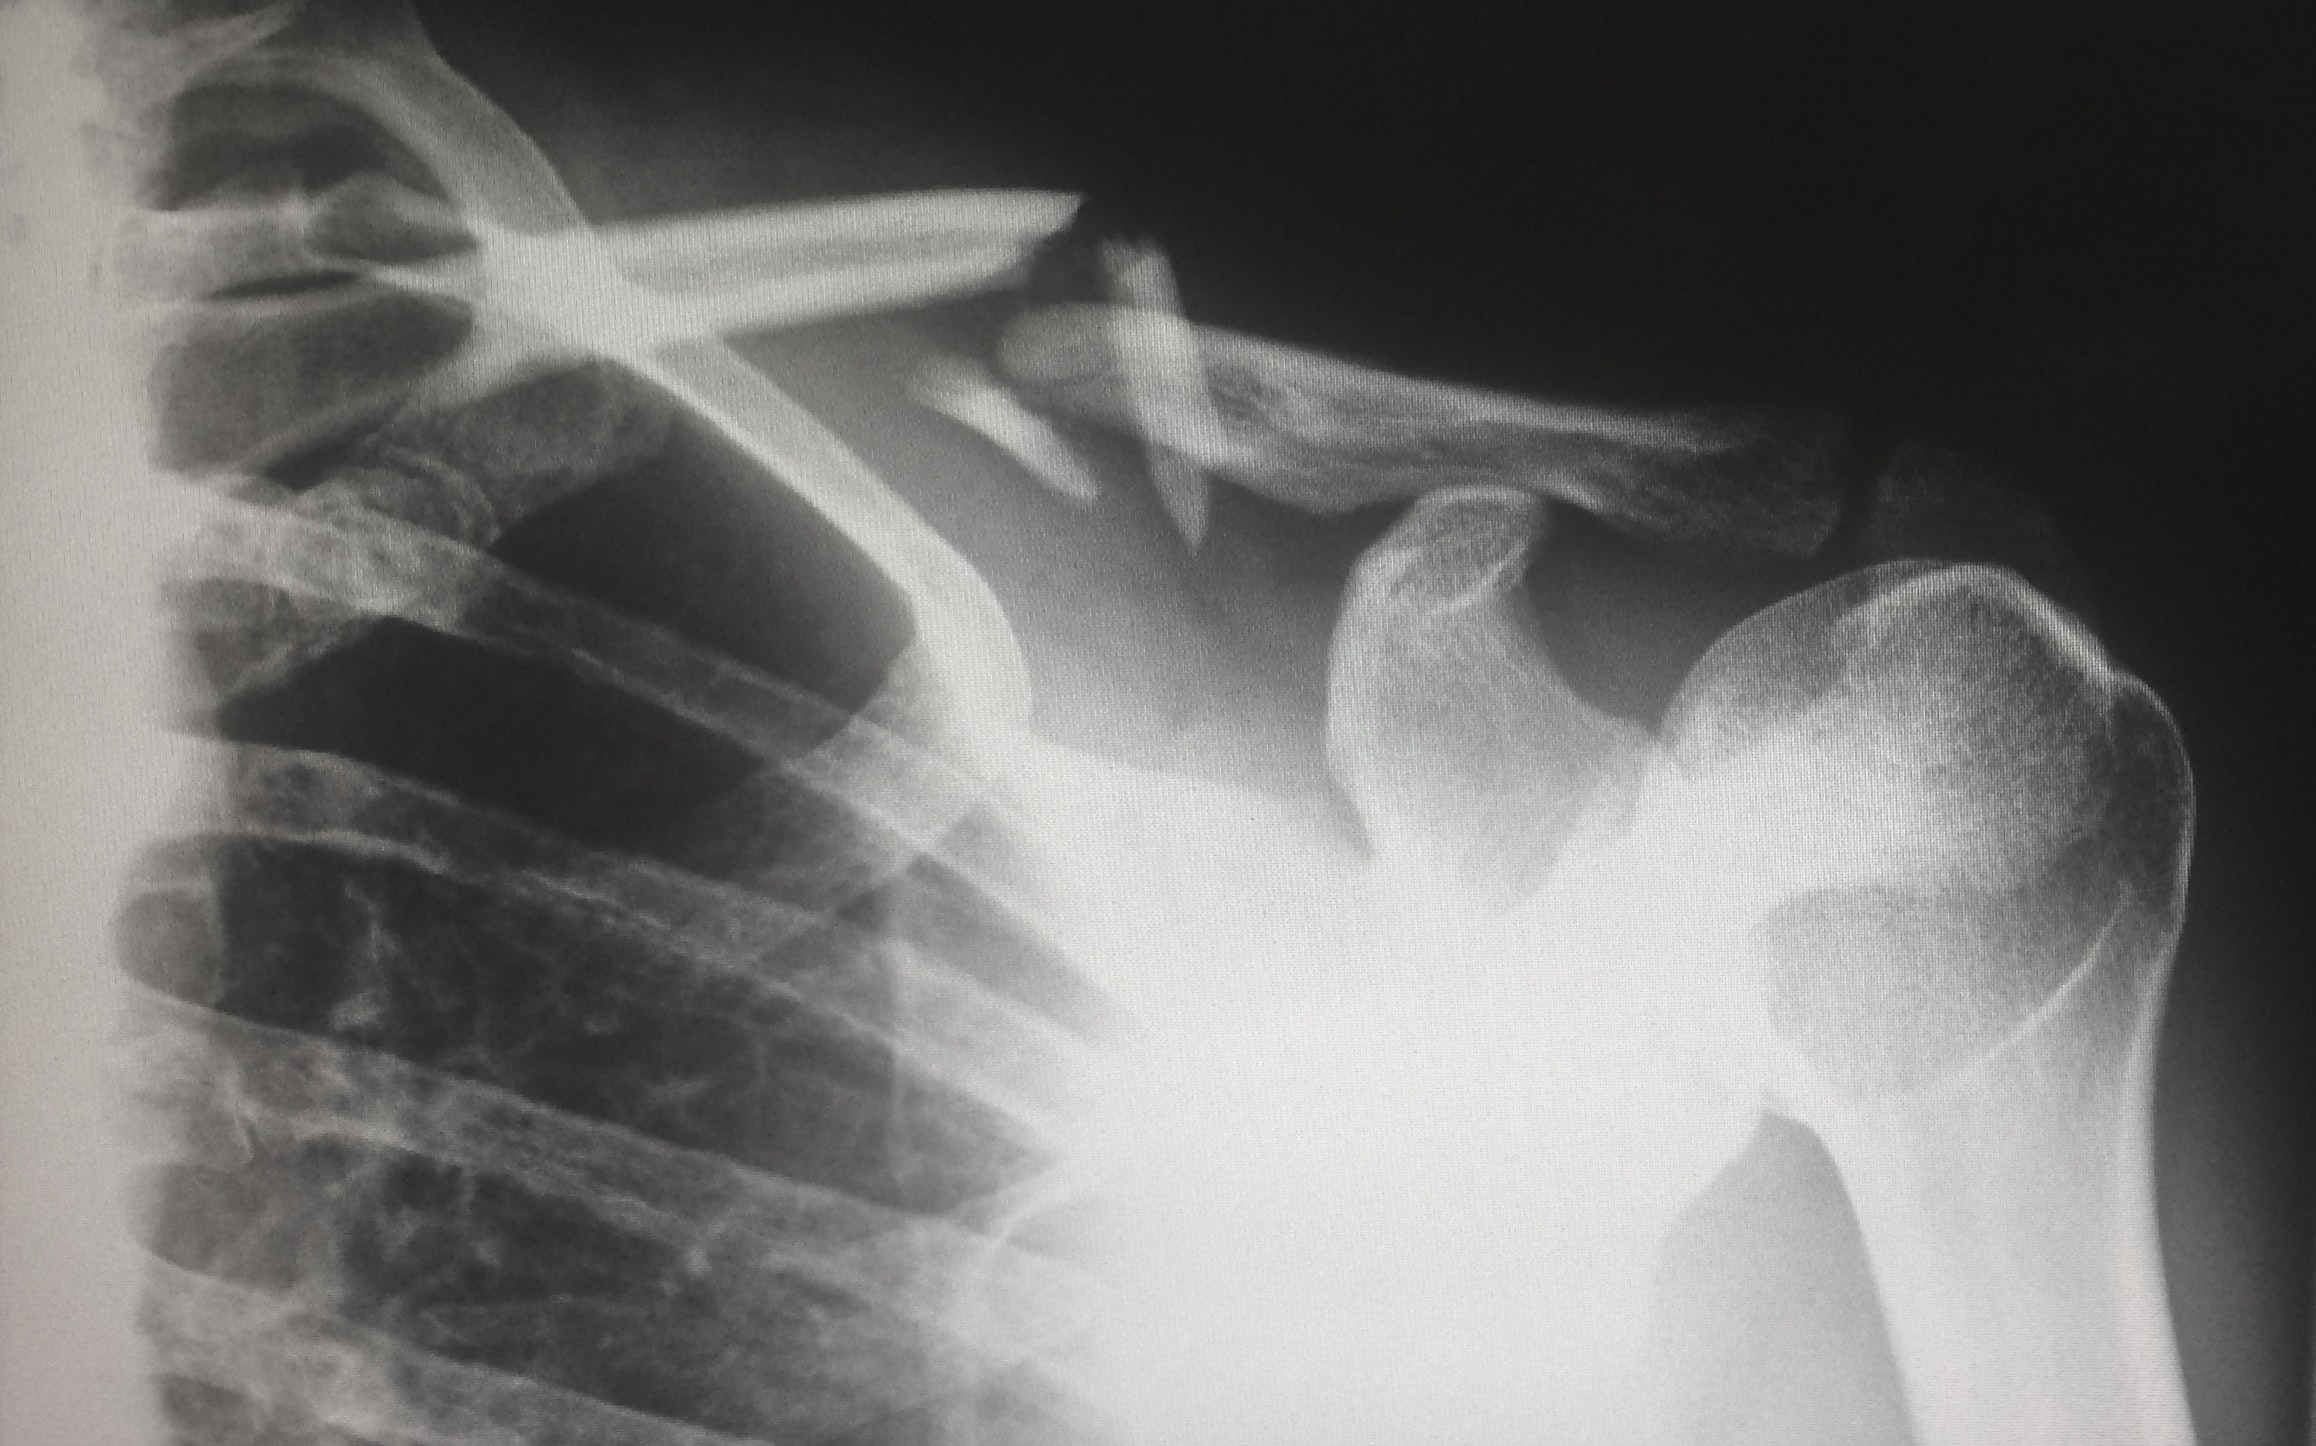

How to maintain bone and joint health during winters?

Motion is life and you need stronger bones and flexible joints to do that. With the onset of winter, the problems of bones and joints ought to increase. It is usually due to...

- By Dr. Ramneek Mahajan

- December 31, 2020

Joint Replacement Centre

We have have dedicated Joint Replacement Centre.